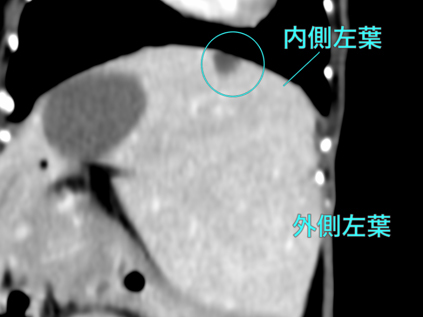

他院にて肝酵素の上昇および肝臓の結節性病変を指摘され、精査および治療のため当院に紹介来院となりました。右肝区域(W39 x L45 x H30mm)、尾状葉乳頭突起(W11 x L16 x H13mm)、内側左葉吻側領域、内側/外側左葉では、結節/腫瘤様の所見を複数認められ最大は外側左葉領域に40mm大の腫瘤が認められました。 本症例は、肝臓内の複数箇所に腫瘤性病変を有し、かつ高齢であることから、全身状態への負担を考慮し、右側および左側に対して2回に分けて肝動脈塞栓術を実施する方針としました。初回の処置として、右肝区域の腫瘤に対する動脈塞栓術を実施し、術後は大きな合併症もなく経過し、術後2日目に退院となりました。

手術前のCT検査での評価